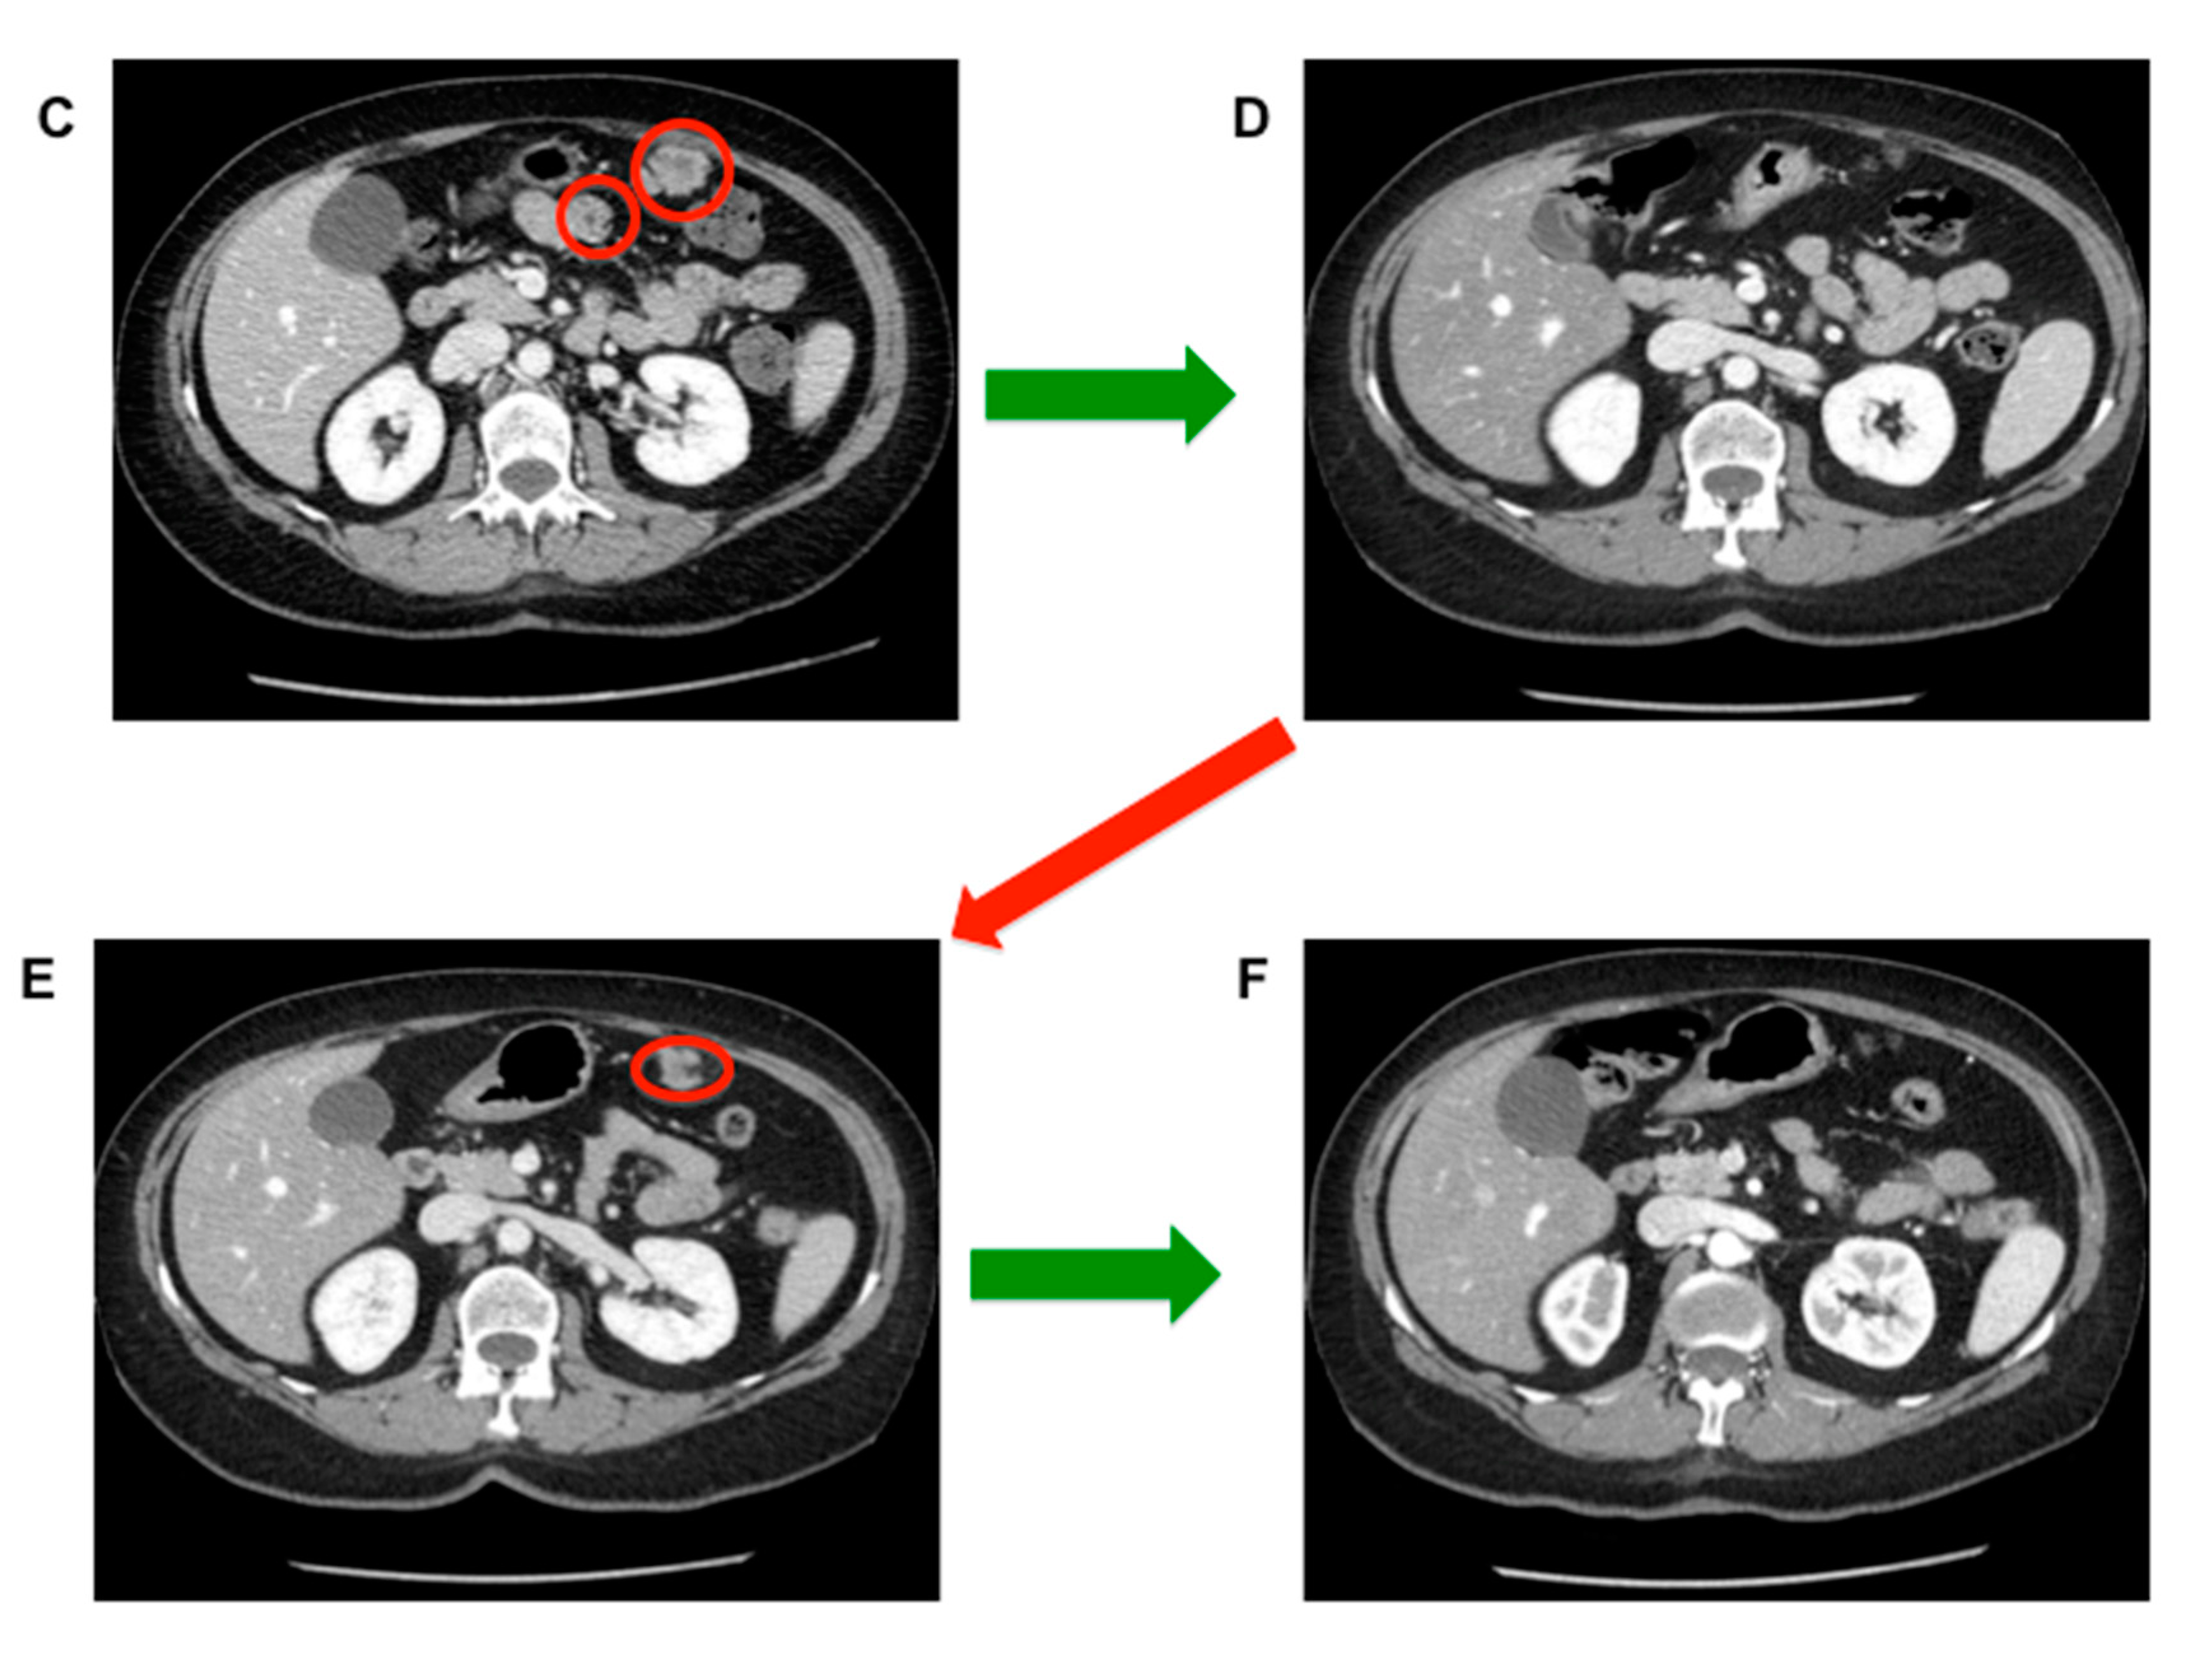

- Stacchiotti, S.; Pantaleo, M.A.; Astolfi, A.; Dagrada, P.; Negri, T.; Dei Tos, A.P.; Indio, V.; Morosi, C.; Gronchi, A.; Colombo, C.; et al. Activity of sunitinib in extraskeletal myxoid condrosarcoma. Eur. J. Cancer 2014, 50, 1657–1664. [Google Scholar] [CrossRef]

- Stacchiotti, S.; Ferrari, S.; Redondo, A.; Hindi, N.; Palmerini, E.; Vaz Salgado, M.A.; Frezza, A.M.; Casali, P.G.; Gutierrez, A.; Lopez-Pousa, A.; et al. Pazopanib for the treatment of advanced extraskeletal myxoid chondrosarcoma: A multicentre, single-arm, phase 2 trial. Lancet Oncol. 2019, 20, 1252–1262. [Google Scholar] [CrossRef]

- Stacchiotti, S.; Dagrada, G.P.; Morosi, C.; Negri, T.; Romanini, A.; Pilotti, S.; Gronchi, A.; Casali, P.G. Extraskeletal myxoid condrosarcoma: Tumor response to sunitinib. Clin. Sarcoma Res. 2012, 2, 22. [Google Scholar] [CrossRef] [PubMed]